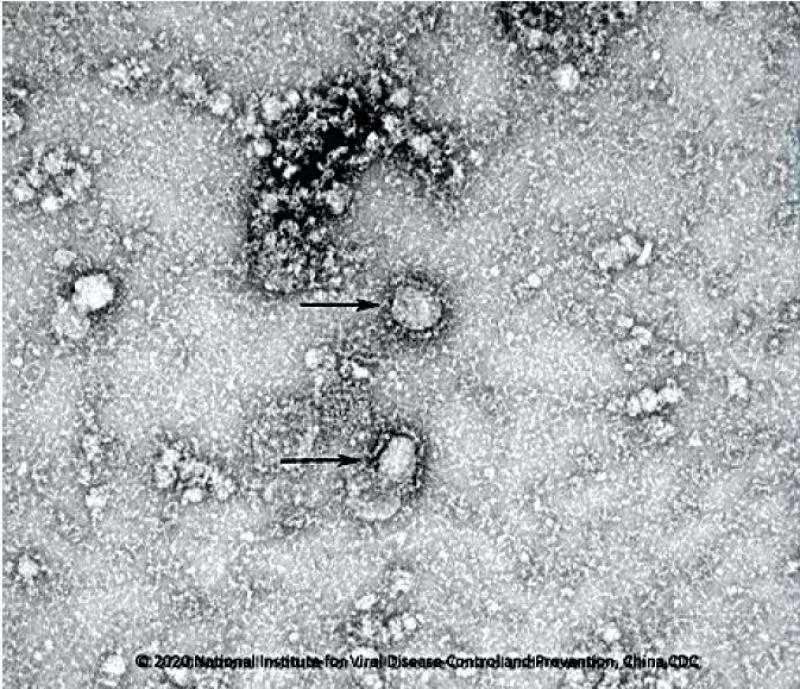

中国疾控中心已成功分离我国首株新型冠状病毒毒种